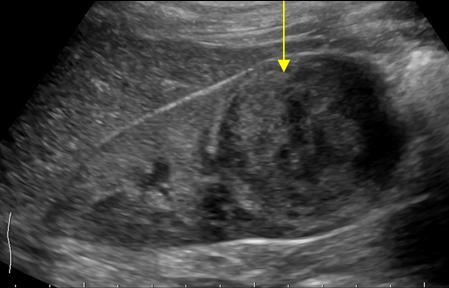

Renal Cell Carcinoma (RCC aka hypernephroma)

- Most common in adults

- If pediatric usually after 11 years old

- solid/cystic, variable echogenicity

- Tumor may invade RV, IVC

Renal Oncocytoma

- Thought to arise from intercalated cells of collecting ducts

- 5-15% of surgical neoplasms

- Central scar, homogenous (non-specific)

Angiomyolipoma

- Benign

- Hyperechoic

- Very common in tuberous sclerosis

- Complications are intratumoral bleeding (hypoechoic areas)